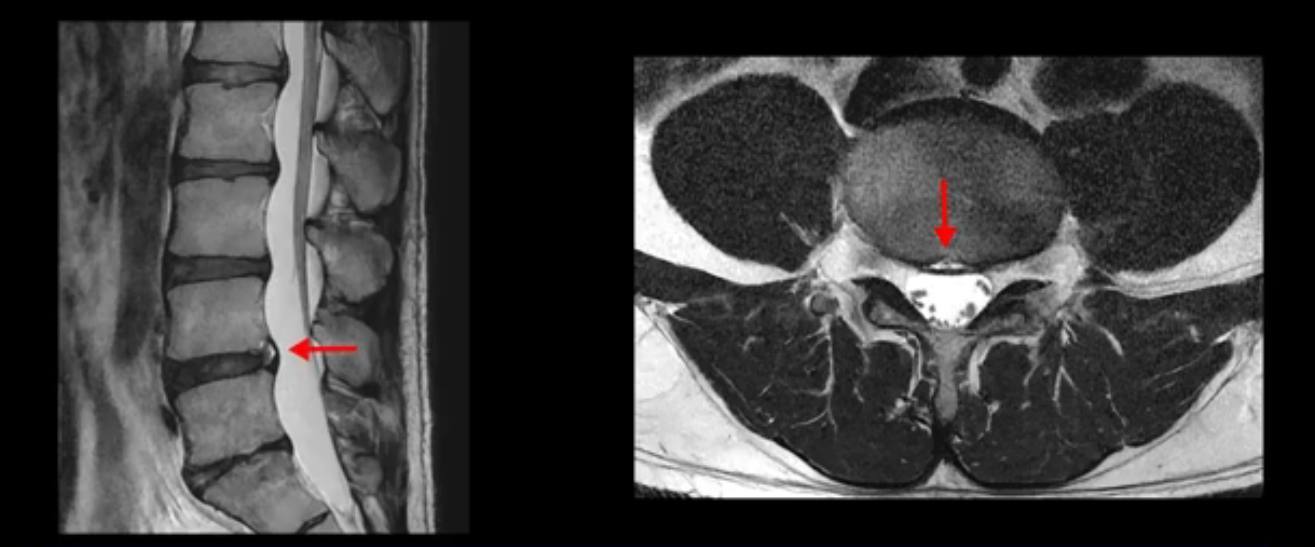

4번 5번은 가운데로 섬유륜이 찢어져서 디스크가 살짝 밀려나와 있지만 역시나 최근에 찢어지고 밀려나온 걸로 판단되지 않고 오래 전에 찢어진 흔적으로 보입니다.

왜 최근에 찢어진 급성이 아니고 오래된 거라고 하는지 이 부분도 뒤에 한꺼번에 설명 드리겠습니다.

5번 1번 역시 가운데로 디스크 조금 밀려 나와있지만 신경 공간 넓이는 아주 넓어서 신경 눌림 있을 거라고 예상이 안됩니다.